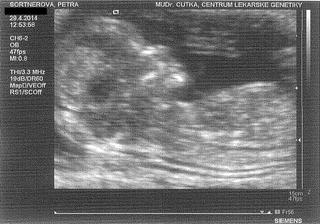

* 29.4.2014 objednané vyšetření v Centru lékařské genetiky - UZ na vývojové vady, tak snad to dopadne dobře - Tak dnešní screening dopadl na 1*... Všechno naprosto dokonalé, miminko zdravé, testy i UZ v pořádku. Mimčo měří 6 cm. Bylo krásně natočené a mávalo nám ručičkama. Paní doktorka nám vše krásně vysvětlila a ukázala... Manžel byl nadšený a je pyšný, protože budeme mít na 80% holčičku 🙂 Jsme nesmírně šťastní 🙂